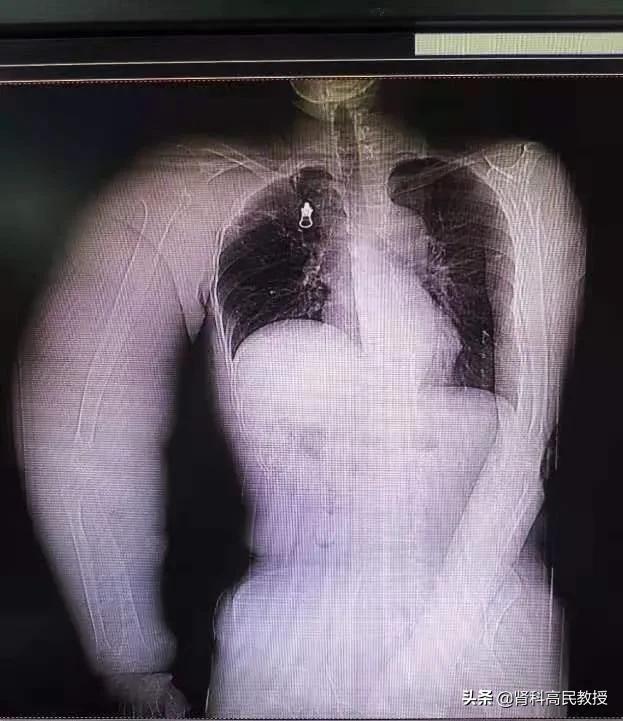

检查的结果,明确了患者血管狭窄的具体部位。结合病史推断,应该是术后放疗造成深静脉血管损伤,以及乳腺癌根治术后局部淋巴回流障碍造成的。

两周后,患者的右上肢从术前的腕围33cm,肘围45cm,腋窝处46cm,恢复到腕围21cm,肘围35cm,腋窝处36cm。